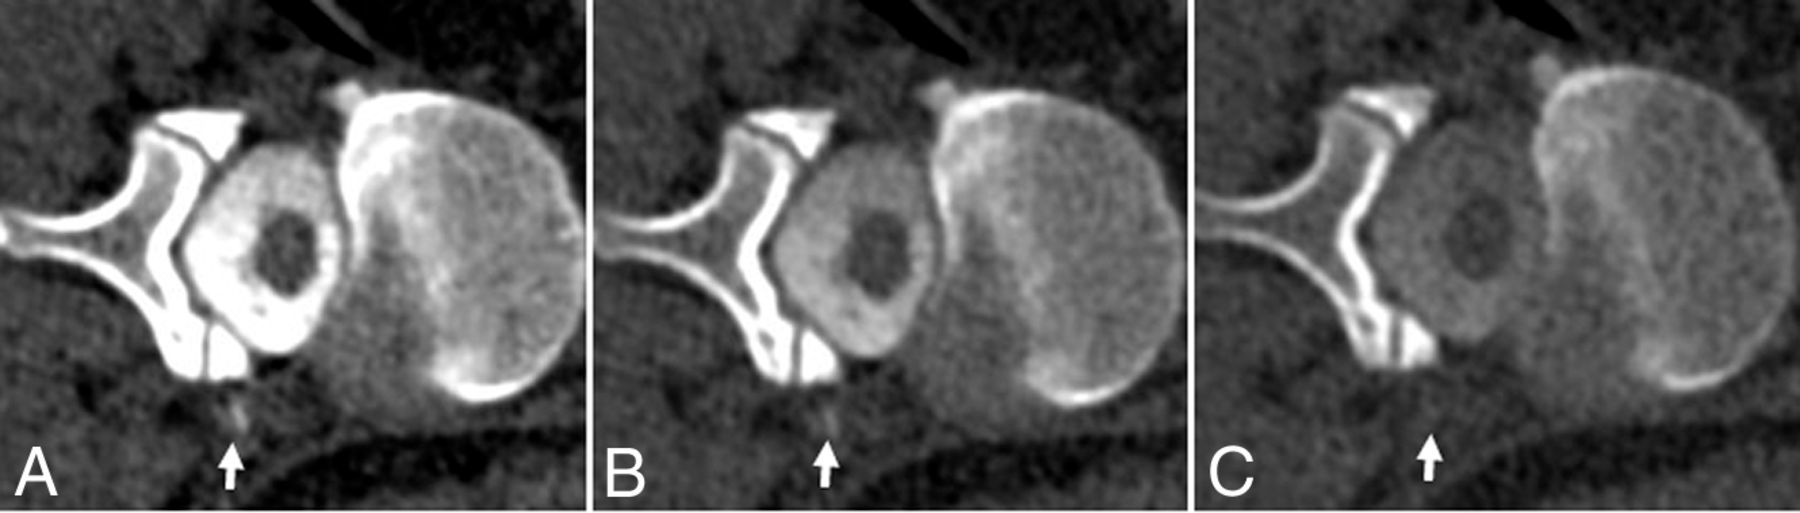

A, 50 -keV VMI. B, 100 kV. C, 150 kV. Case 3: Right-side-down CTM with linear contrast at the right L2–3 neuroforamen (arrows), extending into the paraspinal soft tissues, thought to reflect a vessel associated with contrast leakage at a higher right-T10 distal nerve root sleeve tear (not shown). ROI Hounsfield units: A, 50-keV VMI Hounsfield unit maximum (max): 485 HU; mean, 118 HU. B, 100-kV Hounsfield unit max: 271 HU; mean, 51 HU. C, 150-kV Hounsfield unit max: 151 HU; mean, 16 HU.

A 52-year-old man had a 5-month history of orthostatic headache and pulsatile tinnitus after having his back “cracked” (physical manipulation) at home. He underwent 2 blood patches for presumed CSF leak with transient 2 weeks of partial symptomatic improvement. MR imaging of the brain showed pachymeningeal enhancement, venous sinus engorgement, and effacement of the suprasellar and prepontine cisterns (high-probability Bern score = 7).14 An 111In-DTPA cisternogram showed delayed radionuclide activity ascent supporting SIH. Right LDDSM had negative findings while subsequent same-side-down CTM showed subtle contrast extravasation along the right at L2–3. Subsequent dedicated lateral decubitus dynamic CTM, for localization, demonstrated that the leak originated at T10. A hemilaminectomy and right T10–11 nerve root ligation resulted in durable and sustained complete symptom relief for more than a year.